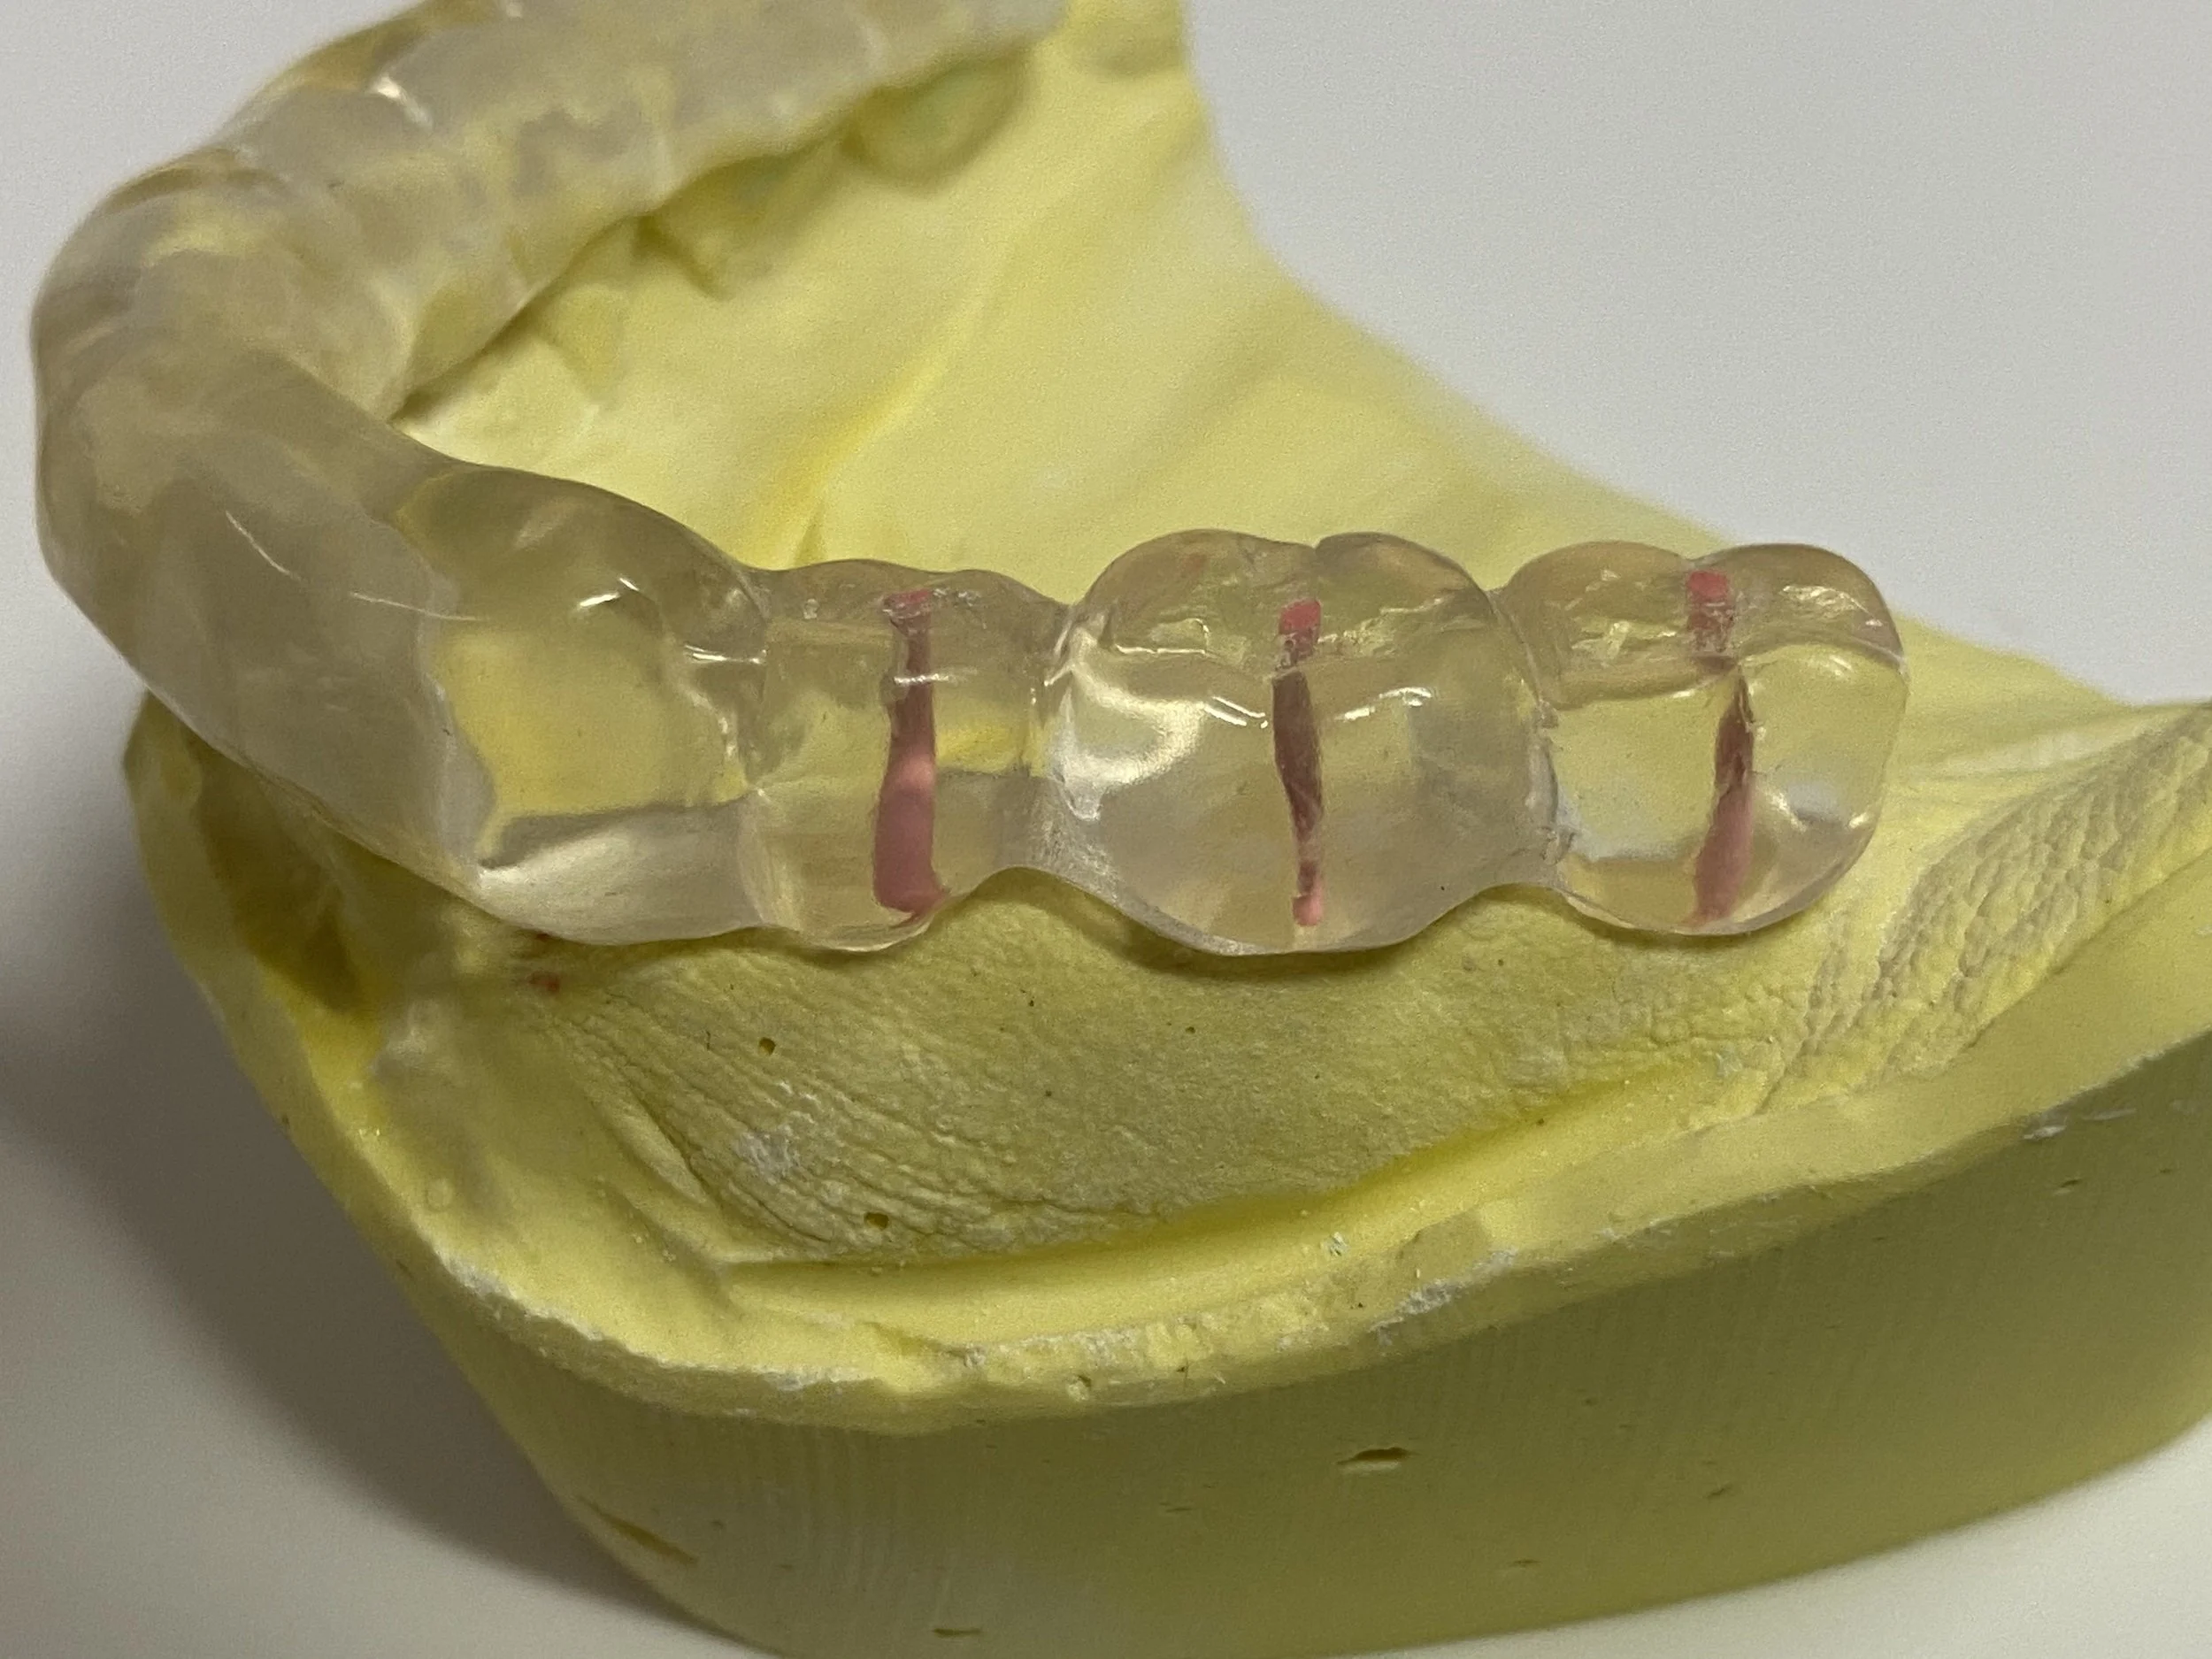

The titanium Atlantis abutments designed and milled in Sweden to be parallel to each other with a 5 degree taper.

The abutments relative to a replica gum line in a plaster model.

4 gold prefabricated Syncone caps 4 mm in height and grooved to retain pink denture acrylic resin. These caps have a frictional sliding fit onto the tapered abutments, which will retain the denture during chewing.

A plaster model with 4 abutments and 4 gold caps inside a waxed implant denture ready for processing.